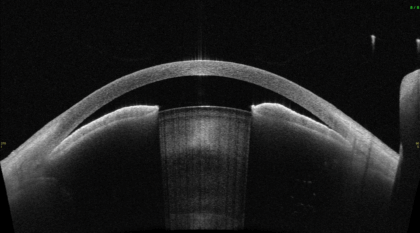

隅角が非常に狭く、眼圧が非常に上昇し緑内障発作となっている状態

白内障手術を行い、隅角が広がった状態

手術前後の画像を重ね合わせると、隅角が広がっていることがよくわかります